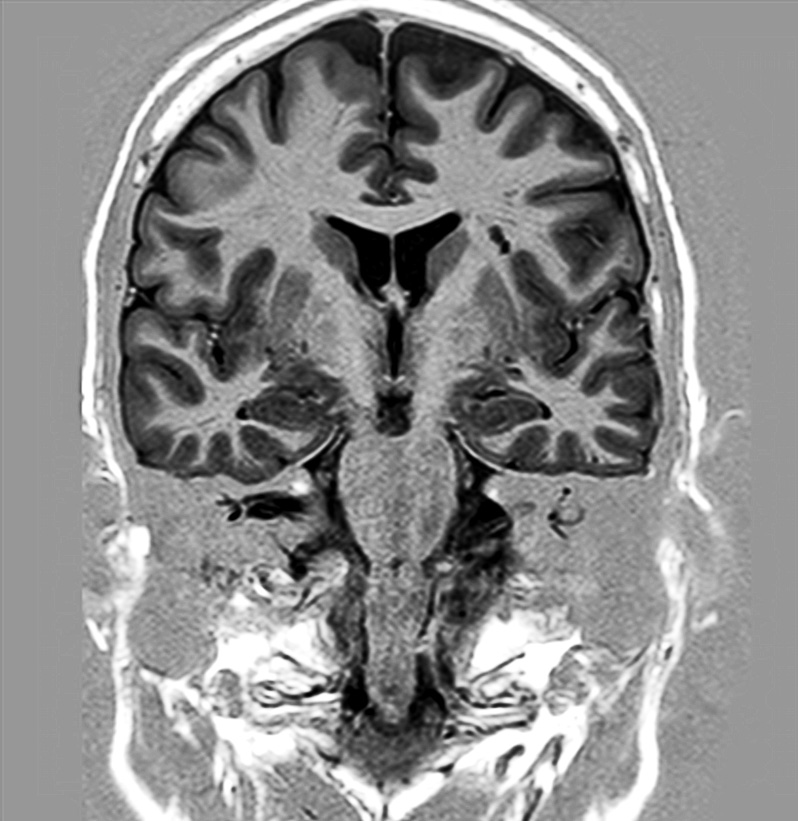

Hippocampus